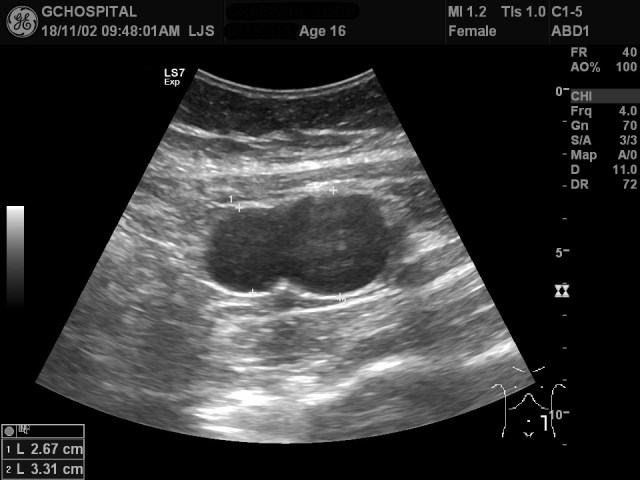

16세 여자 환자로 왼쪽 옆구리의 불편감을 호소해서 초음파 시행하였습니다.

하행결장의 외측에 bilobulated cystic lesion이 보입니다. 한 쪽은 무에코음영이지만, 다른 한쪽의 낭종부위에는 약간의 에코음영이 보입니다. 병변의 전체부위에서 후방에코강조(posterior acoustic enhancement)가 뚜렷하게 보여 낭성병변으로 판단했습니다.

해당 부위를 탐촉자로 눌렀을 때 압통을 보였고, 하행결장과 붙어있어보여서 duplication cyst, lymphangitic cyst 등을 의심해서 CT를 시행했습니다.